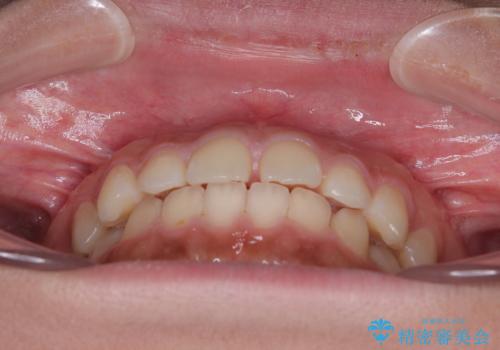

気になるすきっ歯を短期間で改善 インビザライン矯正

- 前歯の隙間を気にして来院された患者様です。

口元の突出感があり、小臼歯4本を抜歯して口元を引っ込める矯正治療も提案しましたが、本人は口元の突出感は気になっていないとのことで、インビザラインにて隙間やデコボコを改善することとしました。

軽度の歯列不正であったため、廉価版のインビザライン・モデレートパッケージにて治療を終えることができました。